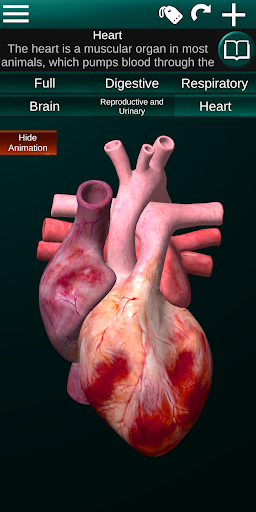

Internal Organs in 3D Anatomy لـ Vodafone Smart N9 Lite

(الأجهزة الداخلية في)

يمكنك هنا تنزيل ملف حزمة تطبيق أندرويد "Internal Organs 3D Anatomy" الخاصة بجهازVodafone Smart N9 Lite مجانًا، نسخة ملف حزمة تطبيق أندرويد - 3.4 للتحميل على Vodafone Smart N9 Lite اضغط ببساطة على هذا الزر. إنه سهل وآمن. نحن نقدم فقط ملفات حزمة تطبيق أندرويد الأصلية. إذا انتهكت أية مواد موجودة في الموقع حقوقك قم بإبلاغنا من خلال